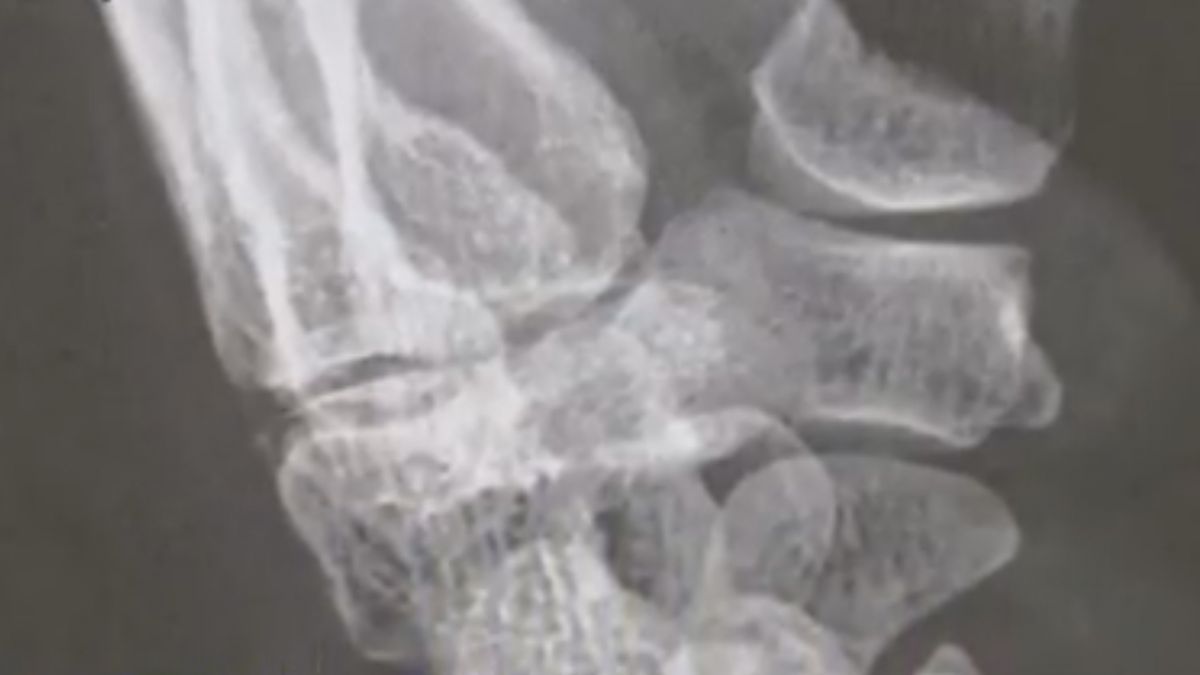

一名婦人,下班離開店家時摔傷手腕骨折,必須休養半年無法工作,和店家申請30多萬

職災

補助,店家卻喊冤

家庭式

經營無法負擔賠償,還說過去婦人偷竊店裡食材,但因為沒有證據只有偷吃10元冰淇淋提告竊盜起訴,這樣的舉動讓婦人的律師認為職災和竊盜根本兩回事,懷疑店家其心可議。